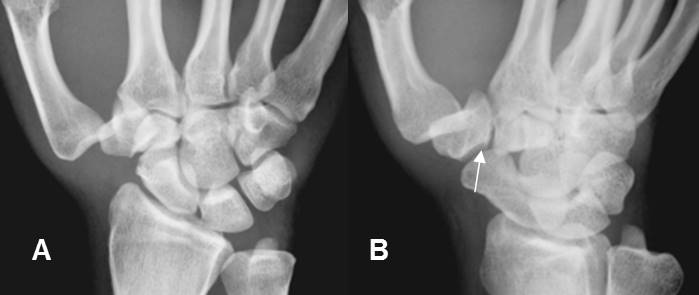

A: Rx AP y B: Rx oblicua. Luxación de articulación carpometacarpiana del pulgar, sin fractura del metacarpiano. Irregularidad en el trapecio, que puede corresponder a fisura.

Fig 175 B. Luxofractura de Bennet.

A: Rx AP y B: Rx oblicua. Subluxación de la articulación carpometacarpiana del pulgar y fractura en la base del metacarpiano, por luxofractura de Bennet.